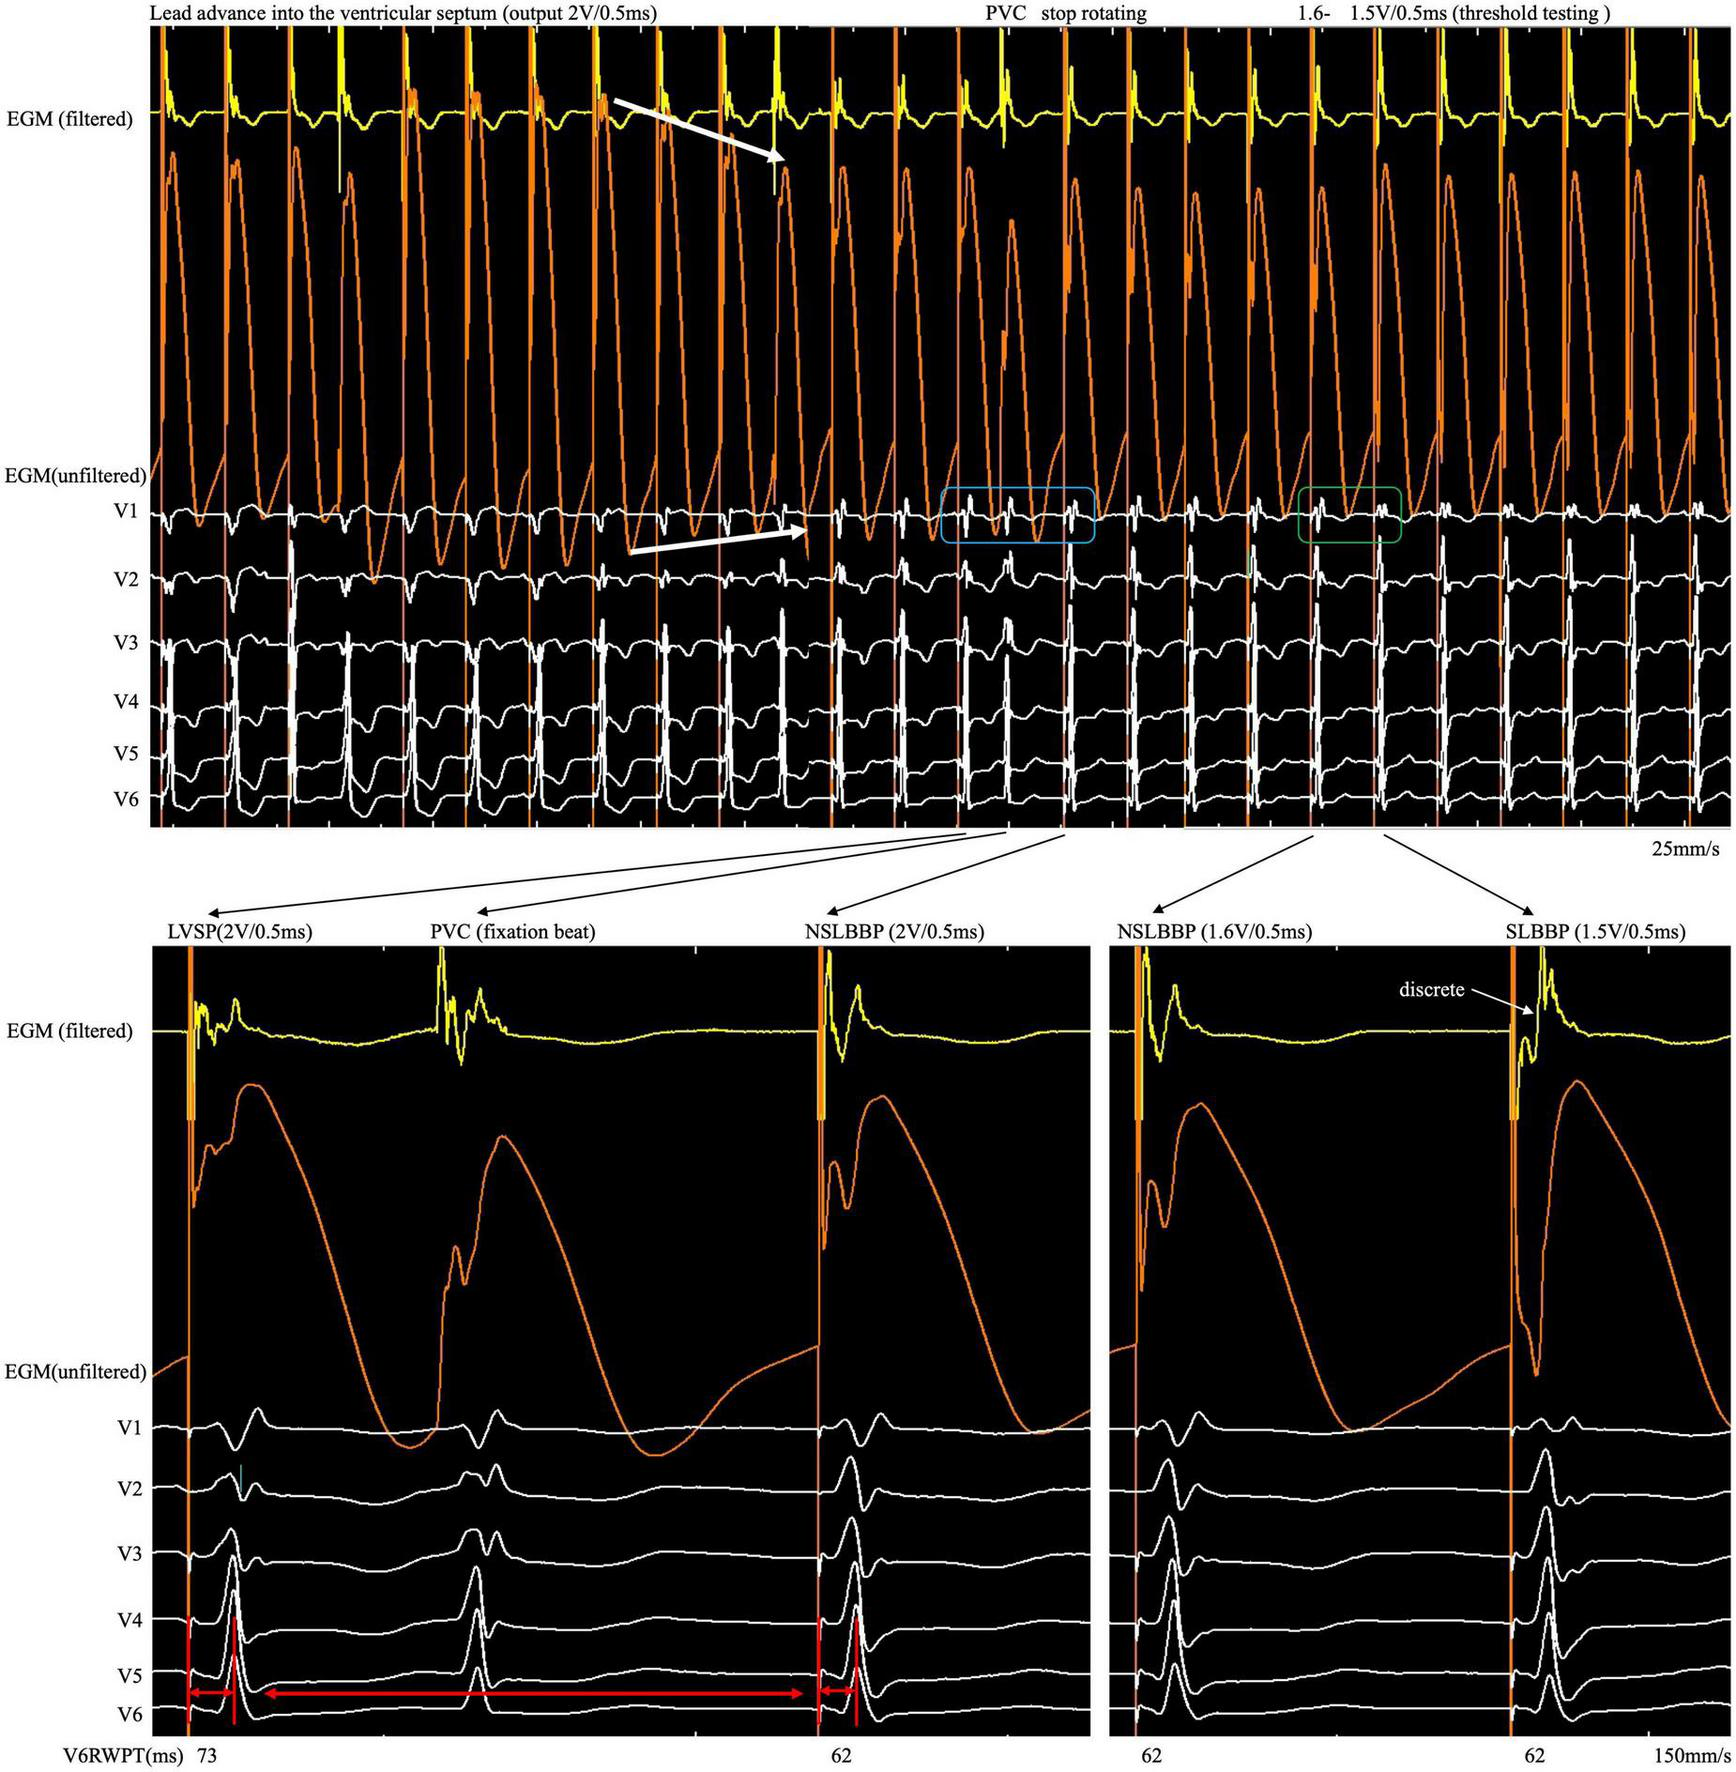

A 76-year-old woman with atrial fibrillation and third-degree atrioventricular block underwent LBBP. Echocardiography examination revealed left ventricular end-diastolic diameter of 44 mm and left ventricular ejection fraction of 75%. Uninterrupted ECG and EGM were recorded on an electrophysiology system using John Jiang’s connecting cable (Xinwell Medical Technology Co., Ltd., Ningbo, Zhejiang, China) (5, 6). In contrast to the interrupted pacing method, this continuous pacing and recording technique enables real-time monitoring of changes in ventricular COI and the paced QRS complex as the lead advances into the interventricular septum. We previously described the LBBP implantation procedure in detail (7, 8). During the entire screw-in process, the COI amplitude increased, peaked, and gradually decreased, followed by a small but significant abrupt decrease (Figure 1). Simultaneously, the impedance dropped from 691 to 532 Ω, and the myocardium capture was lost. This indicates septal perforation. No transition from left ventricular septal pacing to non-selective LBBP (NSLBBP) or NSLBBP to selective LBBP was observed during implantation. With no evidence of LBB capture, the electrode was retracted for the second implant. Repositioning to another site was uneventful. Smooth transition of paced QRS morphology from the LBB block pattern to the right bundle branch block pattern was observed as the lead advanced from the right to left side of the septum. After the COI amplitude peaked, the electrode was rotated very slowly to avoid a sudden drop in COI until the LBB area was reached. An abrupt shortening of the V6 R-wave peak time (V6RWPT) and a discrete EGM were subsequently observed (Figure 2), indicating LBB capture (9). The pacing threshold at the end of procedure was 0.7 V/0.5 ms. The lead was placed at a depth of 14 mm (Supplementary Figure).

FIGURE 2

After the COI amplitude increased to its highest value, the electrode was rotated very slowly to avoid a sudden drop in COI until the LBB area was reached. An abrupt shortening of V6RWPT, discrete EGM and fixation beat were observed. COI, current of injury; LBB, left bundle branch; LBBP, left bundle branch pacing; SLBBP, selective left bundle branch pacing; NSLBBP, non-selective left bundle branch pacing; ECG, electrocardiogram; EGM, intracardiac electrogram; RWPT, R-wave peak time; PVC, premature ventricular complex.

Although changes in impedance and COI were observed during lead fixation, they were insufficient to confirm LBB capture. Because the myocardium and conduction system involve different tissues, they have different electrophysiological characteristics. Different ECG and EGM morphology was observed when different tissues were captured. Therefore, it is necessary to confirm LBB capture, demonstrated as dynamic changes in paced QRS morphology (14). However, subtle but significant changes in paced QRS morphology and EGM are difficult to observe in real time using the intermittent pacing technique but can be recorded by the continuous recording technique. When the rSR pattern suddenly changes to the r’SR pattern in lead V1 (Figure 2, blue rectangle) and V6RWPT abruptly shortens between the morphology of two adjacent paced QRS complexes (Figure 2, red arrow), the implantation process should be ceased, and threshold testing should be performed. When reducing the output, the discrete component in the filtered EGM and transition from the r’SR pattern to the M pattern on the ECG (Figure 2, green rectangle) are observed. In high- and low-output testing, V6RWPT is constant and remains the shortest value requiring measurement. If the V6RWPT of the high output is shorter than that of the low output, the lead must be screwed in slightly to keep the V6RWPT of the high and low outputs constant.